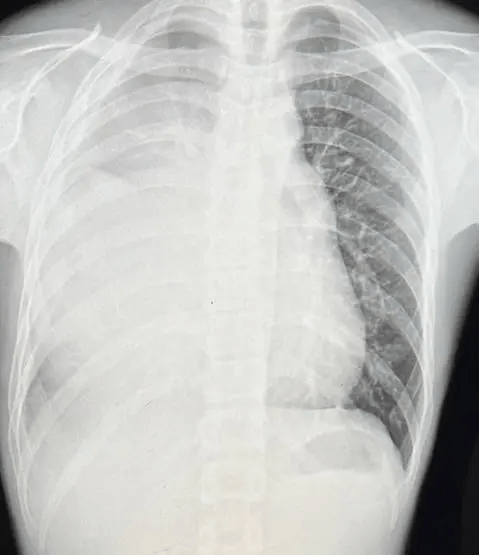

该名21岁男子日前在Dcard讨论区发文,讲述自己发现患癌的过程及抗癌经历。他表示自己在今年7月8日突然感到胸痛,于是到诊所求医,照X光后发现肺部白了一片。医生以为他患上肺炎,于是转介至医院的胸腔内科,并进行电脑断层和磁力共振扫描检查,结果发现其纵膈腔有一个15厘米巨大肿瘤,证实是「生殖细胞肿瘤第4期」。